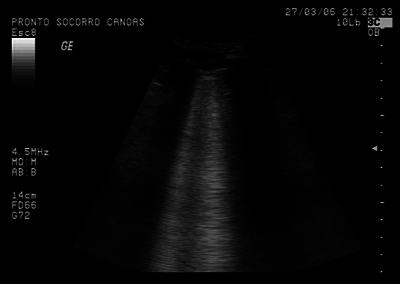

Simon Hayward (aka @sonophysio) is a great advocate of lung ultrasound in the critical care patient. He currently is running a very popular course with one of his medical colleagues to help introduce people to this technique. He is busy! We talk about the reasons for doing so as well as discussing the recent conference he went to in South Africa for all kinds of therapists.